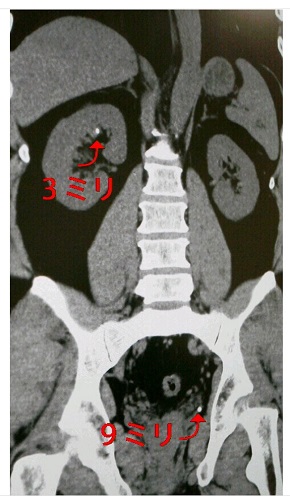

約半年前に9ミリと3ミリの尿路結石があると診断された富澤さんでしたが、今回、9ミリのほうが排出。前日25日に「劇場版『鬼滅の刃』無限列車編」(フジテレビ系)が放送されている最中のことだったようで、「炭治郎が水の呼吸、煉獄さんが炎の呼吸を繰り出している同じ時、富澤は尿の呼吸を繰り出した。『おぉぉぉーっ!! 出ろぉーっ!!』スポンッ!! あ……で、出たぁっ!! 『煉獄さーーーん!!』思わず叫ぶ。痛みは無かった」と迫真のレポートをしています。